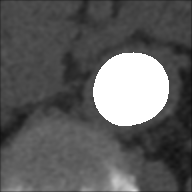

In this version of the algorithm (updated compared to the one described in [30]), the calcium plaques are excluded from the patent lumen of the vessel and therefore visible in the processed image (in black), as we can observe also from Tables 3 and 4. The advantage of removing these structures during the extraction process leads to a more accurate and faithful evaluation of the indices. This observation is illustrated in Figure 6, where we present a comparison of results for a single slice obtained using the previous algorithm version, which does not remove calcium plaques from both the basal and the CM images, and the new algorithm version. The performance improvement is evident, particularly in the DCI index, where a difference is observed: of white pixels are accurately classified with the old version, compared to with the new version. Finally we highlight how, in the new version of the algorithm, the removal of the calcium plaques from both the basal and the CM images produces a different extraction of the patent lumen of the vessel, which in addition to being compatible with the algorithm’s steps, also turns out to be more accurate.

| Basal image | CM image | Version | Extracted | Colored map | Indices |

![]() |

Old | ![]() |

DCI: 0.824 |

| TI: 0.700 | |||||

| Em: 0.300 | |||||

| : -0.192 | |||||

| New | ![]() |

DCI: 0.894 | ||

| TI: 0.809 | |||||

| Em: 0.191 | |||||

| : -0.075 |